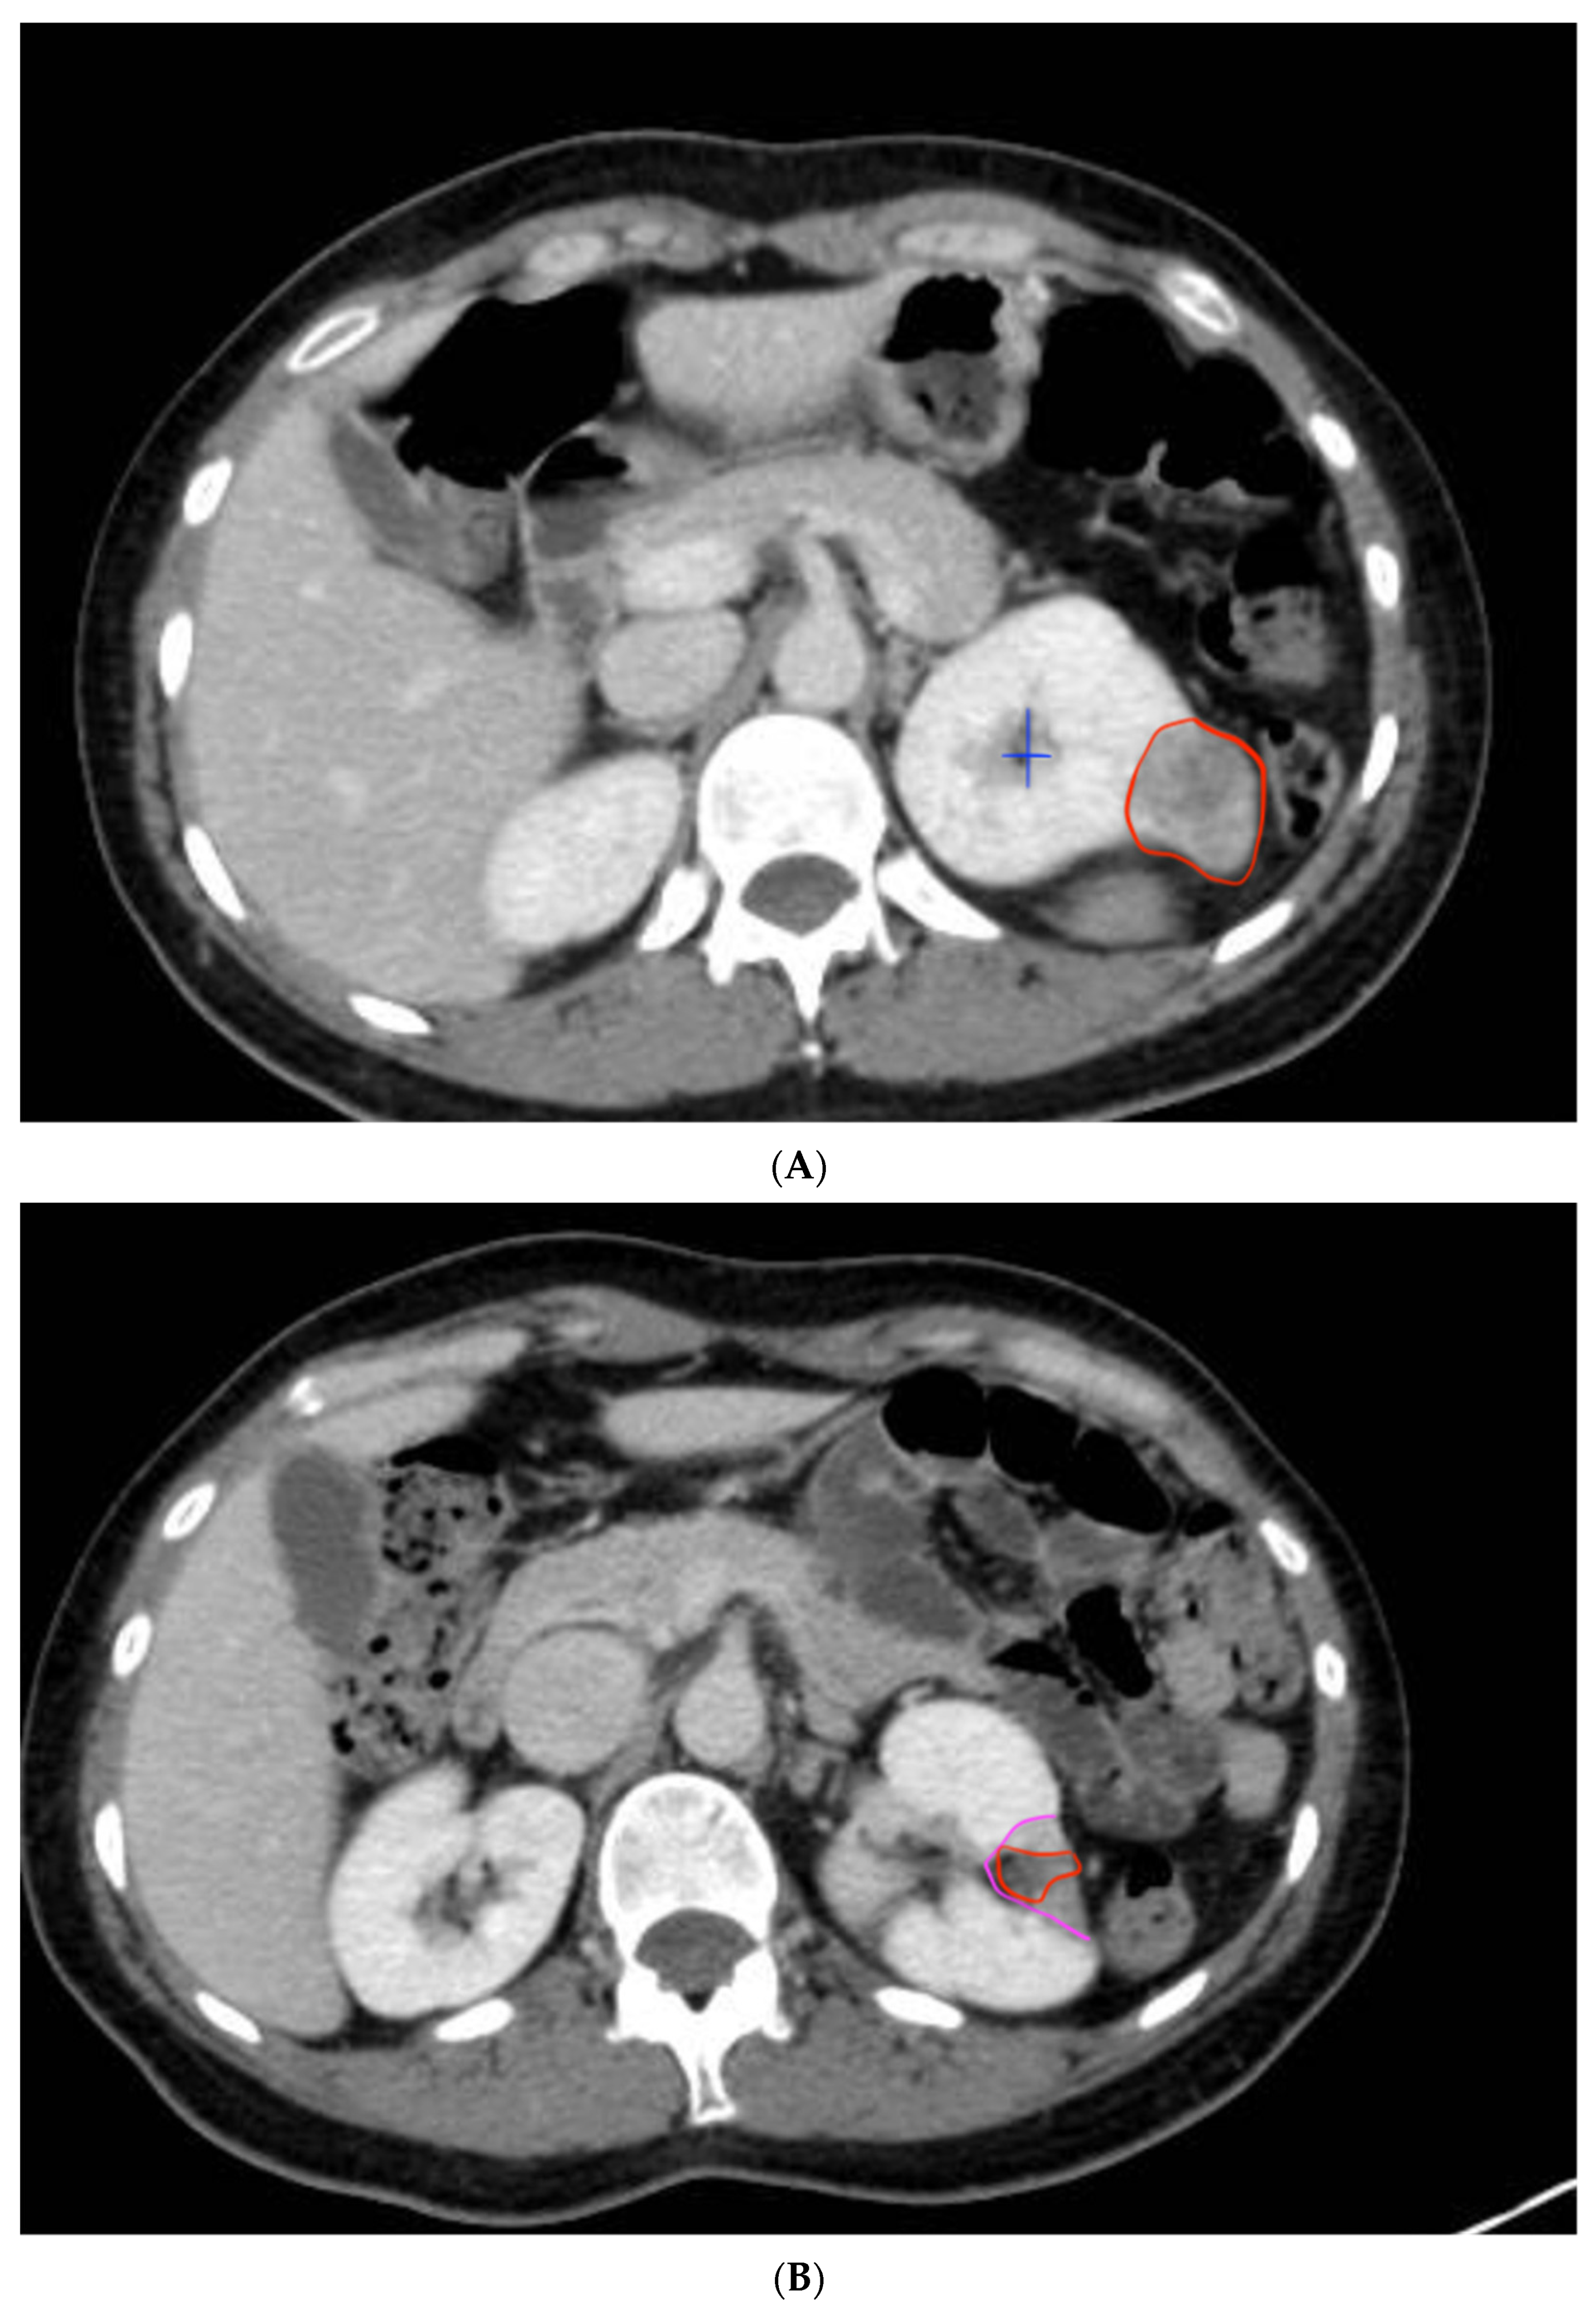

2.2. Procedure and Technique